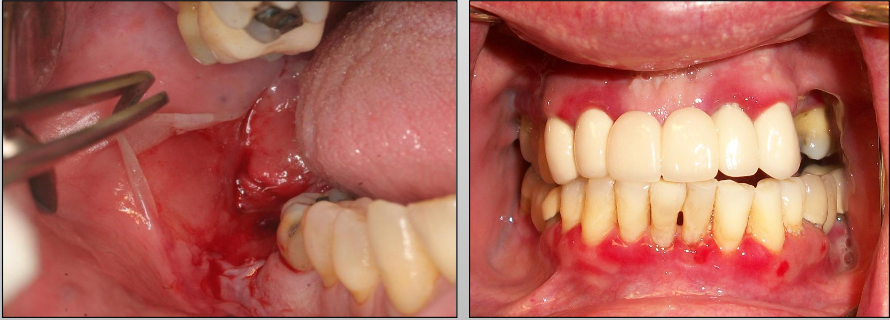

What is Mucous Membrane Pemphigoid?

A chronic autoimmune disease that affects the oral mucosa, conjunctiva, genital mucosa, and skin

Where might you find Mucous Membrane Pemphigoid?

Skin and mucosa (mouth, genital, eye)

And intraorally: gingiva (most common)

What is a unique clinical feature of Mucous Membrane Pemphigoid?

Symblepharons (fibrous scars) along the eye